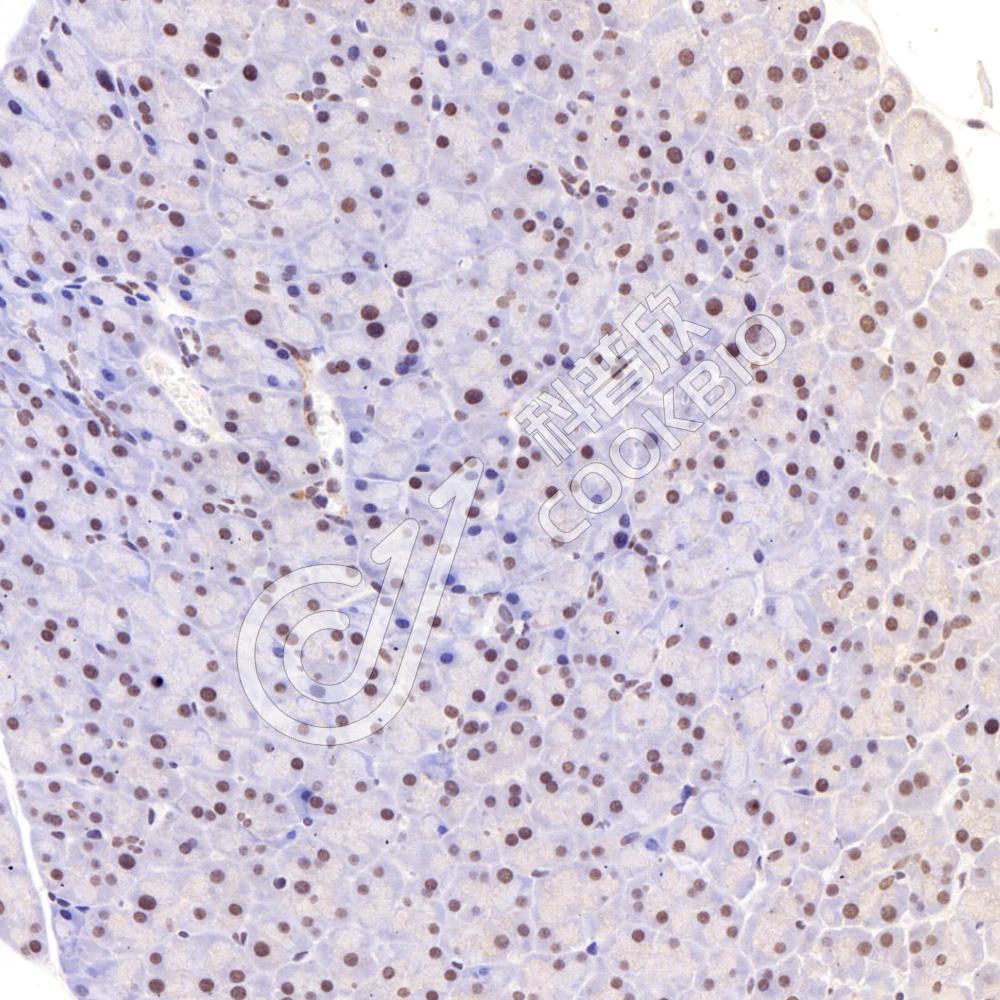

IHC检测HSPA6蛋白(货号 K1334980).

样品: 小鼠肺, 4%多聚甲醛 (货号KSG1101) 固定12-24小时.

抗原修复: 柠檬酸抗原修复液(干粉, pH 6.0) (KSG1201), 98℃, 20分钟.

—抗: 1: 1300稀释, 4℃ 孵育过夜.

二抗: S-vision免疫组化多聚二抗(山羊抗兔),即用型 (货号KB3906), 室温孵育20分钟.